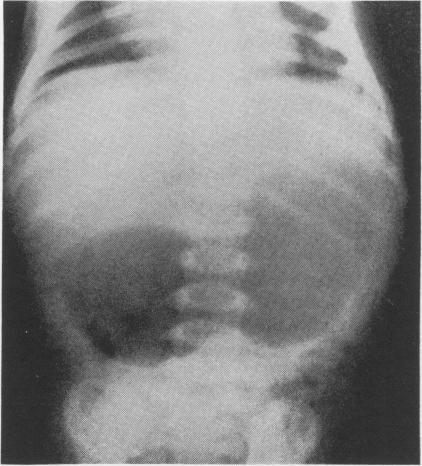

Gastric and intestinal obstructions in the newborn and infants; clinical review of 61 cases.

J Natl Med Assoc. 1958 Jan;50(1):36-9.